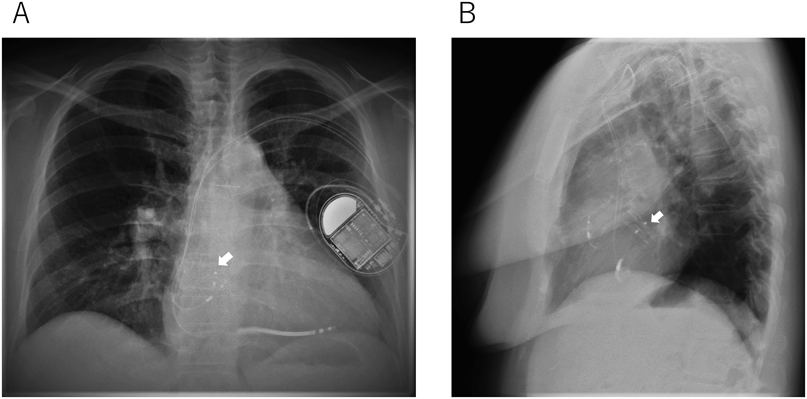

Fig. 2 Adult women repaired tetralogy of Fallot with sustained ventricular tachycardia and residual atrial shunt. She underwent atrial septal defect closure using atrial septal defect occluder before transvenous ICD implantation to prevent lead related systemic thrombosis

A: Chest X-ray (frontal view). B: Chest X-ray (lateral view). White arrow: atrial septal defect occluder. ICD, implantable cardioverter defibrillator